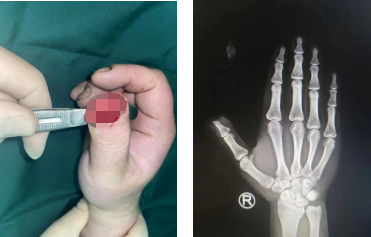

术前

第二天,郑大卫主任医师、潘勇副主任医师与刘绍利主治医生手术团队为患者进行了右拇指清创+游离第一趾酶甲骨瓣再造术。

术后